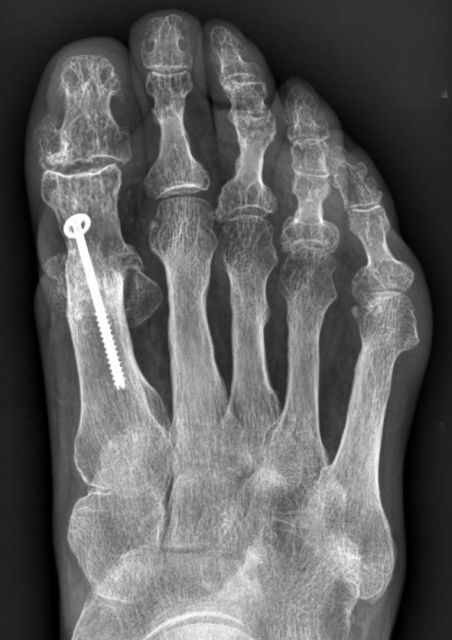

Die operative Versteifung des Großzehengrundgelenks stellt bis heute das therapeutische Standardverfahren beim symptomatischen schweren Hallux rigidus mit geringem Komplikationsrisiko dar. Häufig betrifft diese Erkrankung Patienten in höherem Lebensalter mit entsprechenden Begleiterkrankungen. Bei Patienten mit peripheren Durchblutungsstörungen oder empfindlicher lokaler Hautsituation, wie z.B. bei rheumatoider Arthritis besteht bei offenem Operationverfahren ein erhöhtes Risiko einer Wundinfektion und in Folge auch Pseudarthrose. Bei offenen Arthrodeseverfahren am Großzehengrundgelenk wird das generelle Komplikationsrisiko bezogen auf Infektion und Pseudarthrose mit 10-16% angegeben und ist bei entsprechenden Vorerkrankungen zusätzlich erhöht. Minimalinvasive Operationstechniken am Vorfuß zeigen ein niedriges Komplikationsrisiko. Die zusätzliche Verwendung eines Arthroskops erlaubt bei der Arthrodese des Großzehengrundgelenks eine visuelle Kontrolle der knöchernen Kontaktflächen, ist aber technisch anspruchsvoller.

Mit dieser Operationstechnik kann mit überschaubarem Risiko gerade bei Patienten mit hohem Wundinfektionsrisiko ein stabiles Ergebnis erreicht werden.